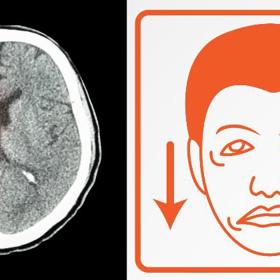

Mrtvice má řadu příznaků lišících se podle toho, která část mozku je zasažena. Spolehlivě ji lze rozpoznat jednoduchým testem tří základních příznaků, jež se u nemocného projeví – pokles koutku úst, ochrnutí či slabost paže a porucha řeči. Pokud se objeví byť jen jeden z těchto příznaků, je nezbytné neprodleně přivolat záchrannou službu.